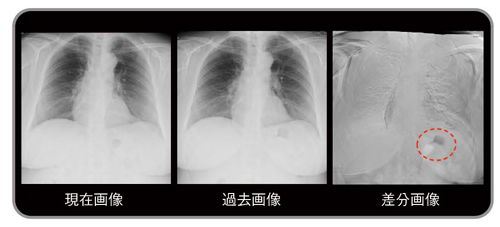

アーチファクトの生じやすい部位としては,肋骨,鎖骨,心血管,横隔膜,乳房,大胸筋,胃泡などがある(図7〜9)。実際の読影時には,現在画像,過去画像,差分画像の三者を見比べることで,アーチファクトによる偽像か否かの判断は比較的容易である。

図9 アーチファクト症例:胃泡の形の変化による